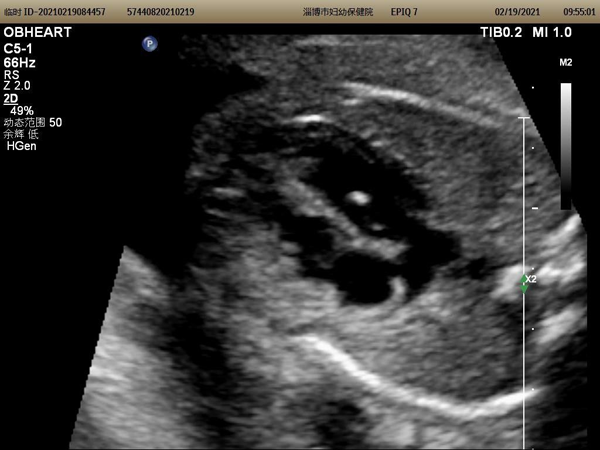

第一步我们要明确什么是左室强光点(Echogenic intracardiac focus简称EIF)

左室强光点是指心脏一侧心室腔内游离区域的点状孤立灶性回声。是一种超声影像学表现而不是一种心脏畸形,更不是一种胎儿心脏异常的超声诊断。有报道显示其发生率在0.5%~20%左右。可单发也可多发,左室多见,随孕期增加回声逐渐减弱,最迟约1岁消失。